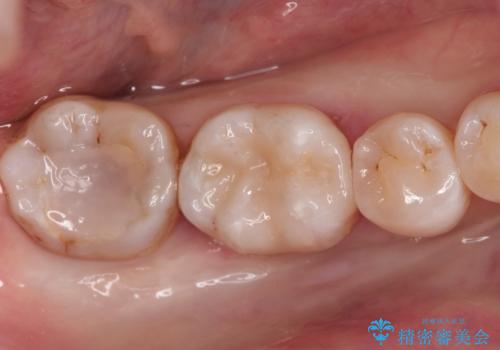

メタルフリー セラミックインレーによる治療

- 金属の詰め物を白くしたいと来院された患者様です。

セラミックインレーによって治療を行いました。

当院でのセラミックインレーはすべてe-maxと呼ばれる高強度セラミックにて製作されます。

また、製作方法もプレスと呼ばれる方法を用いることで精度を高めています。